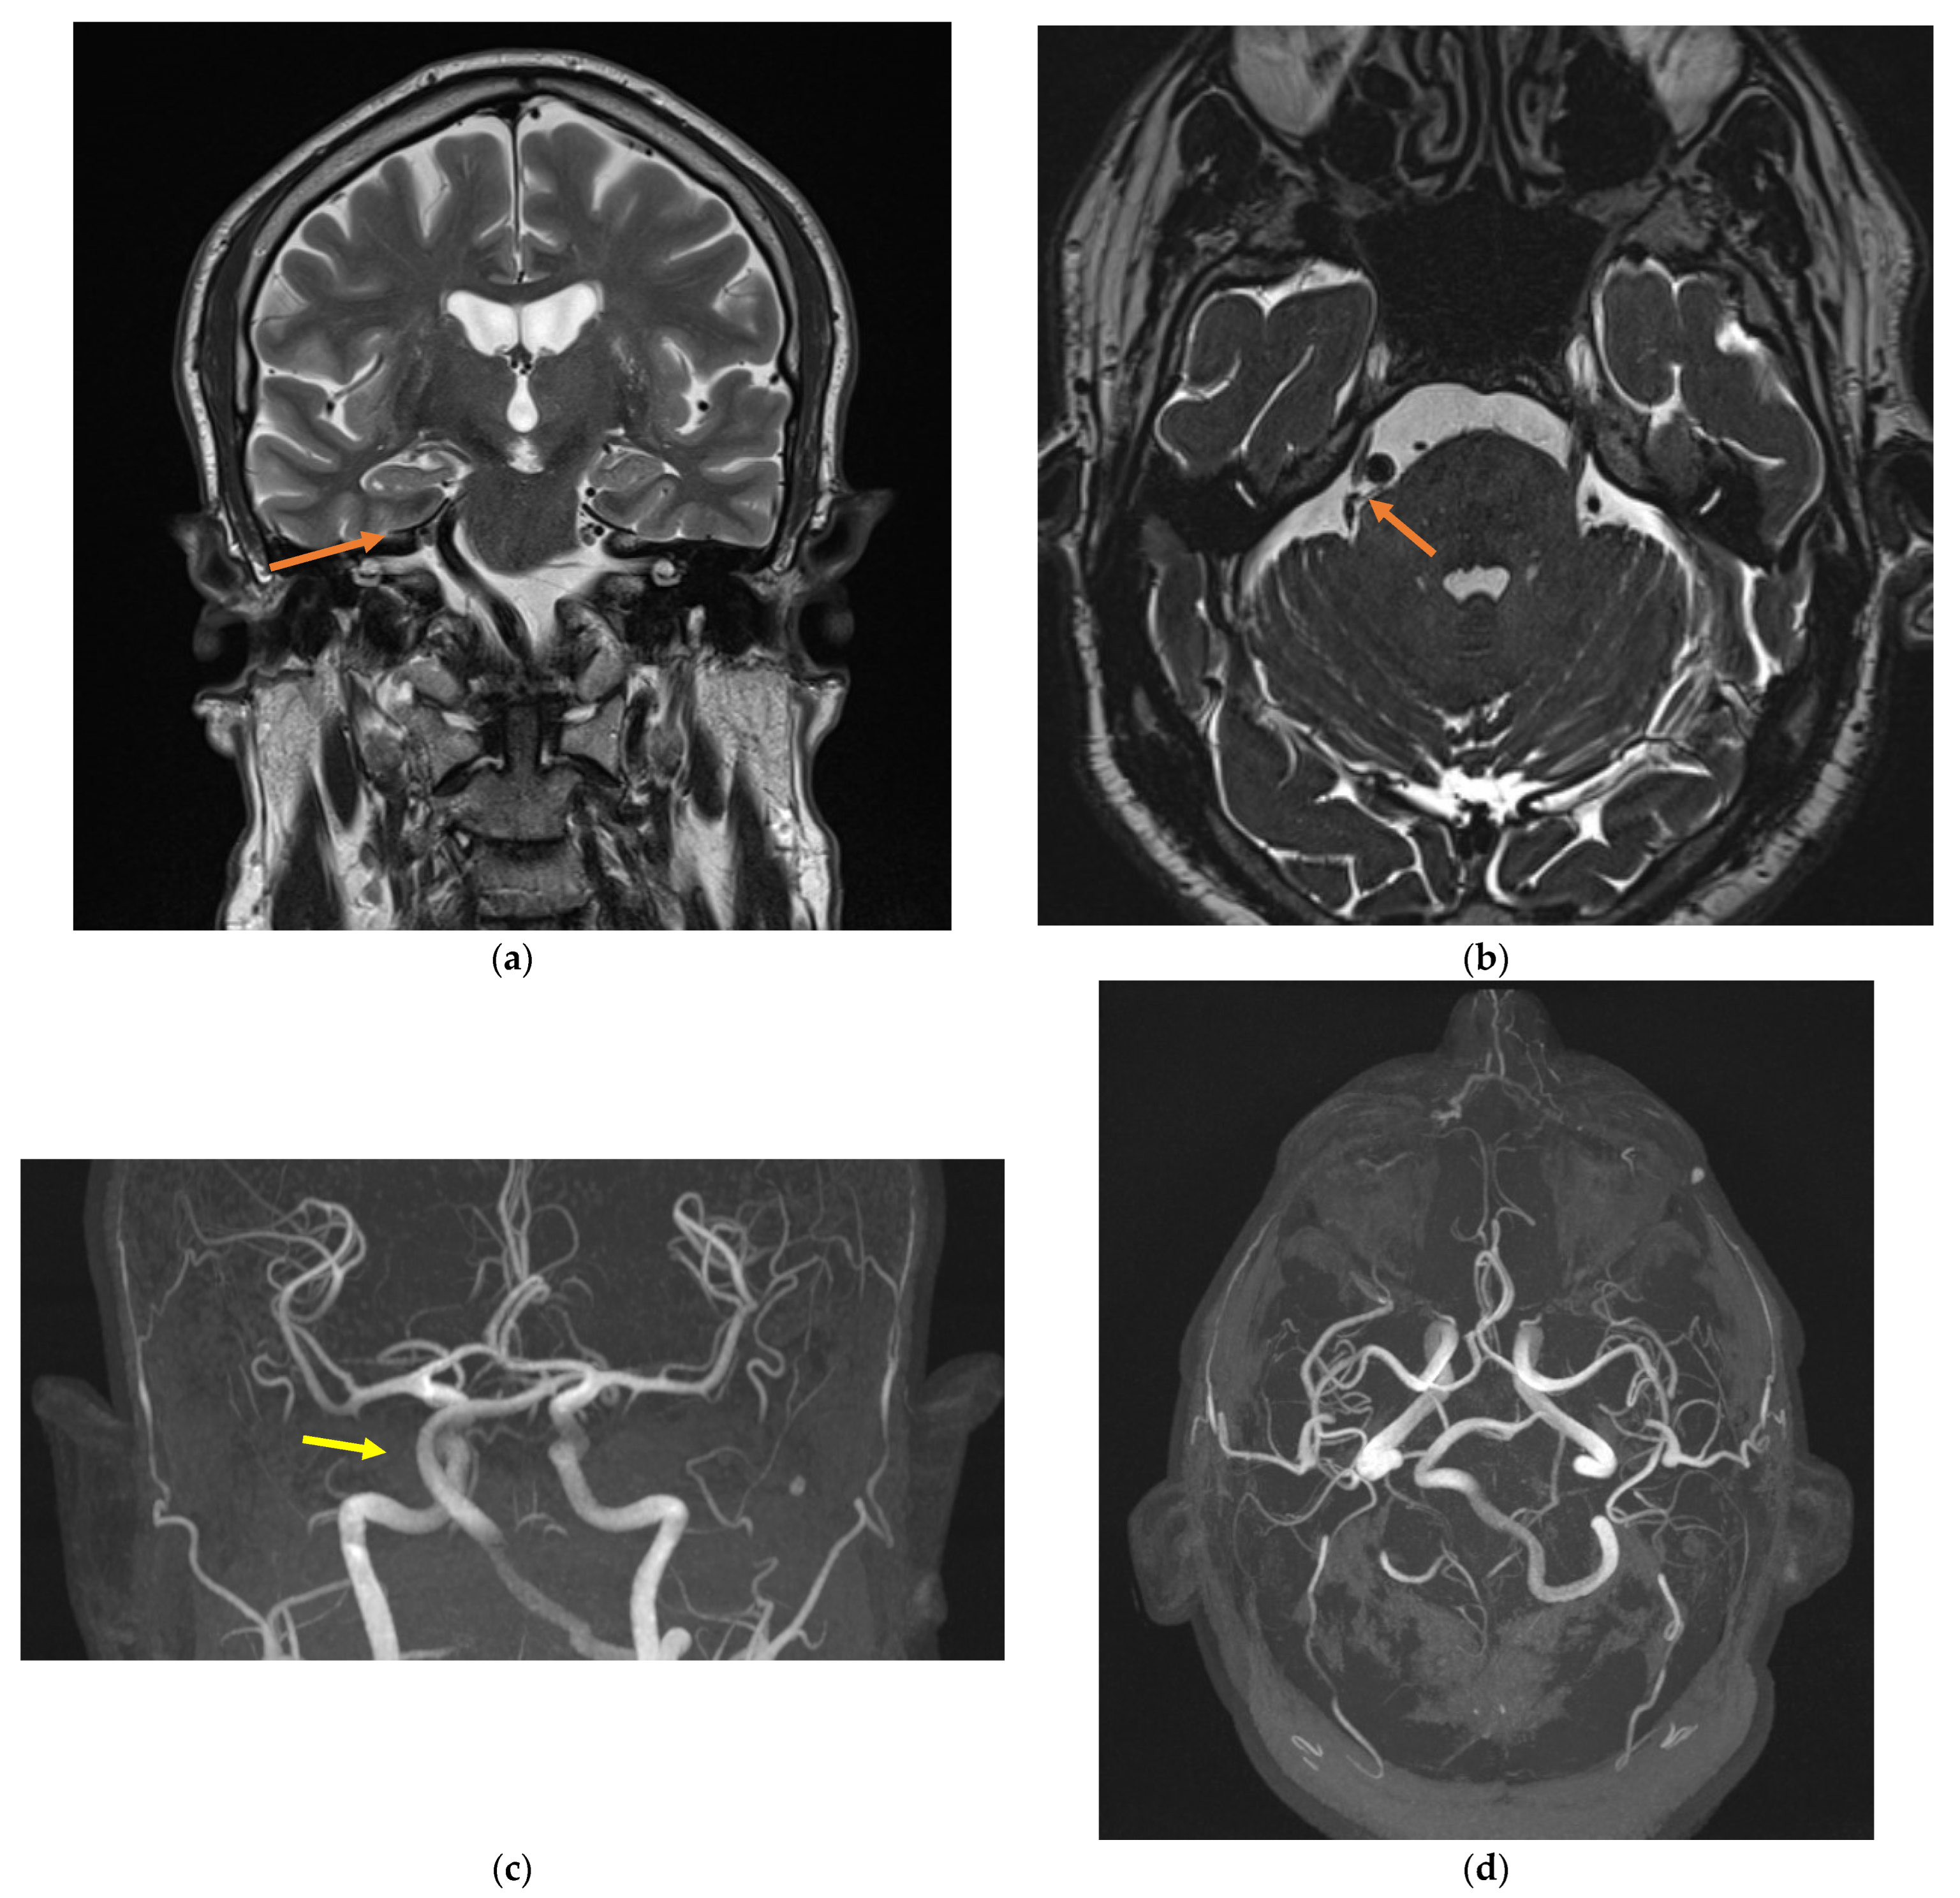

2. Case Presentation